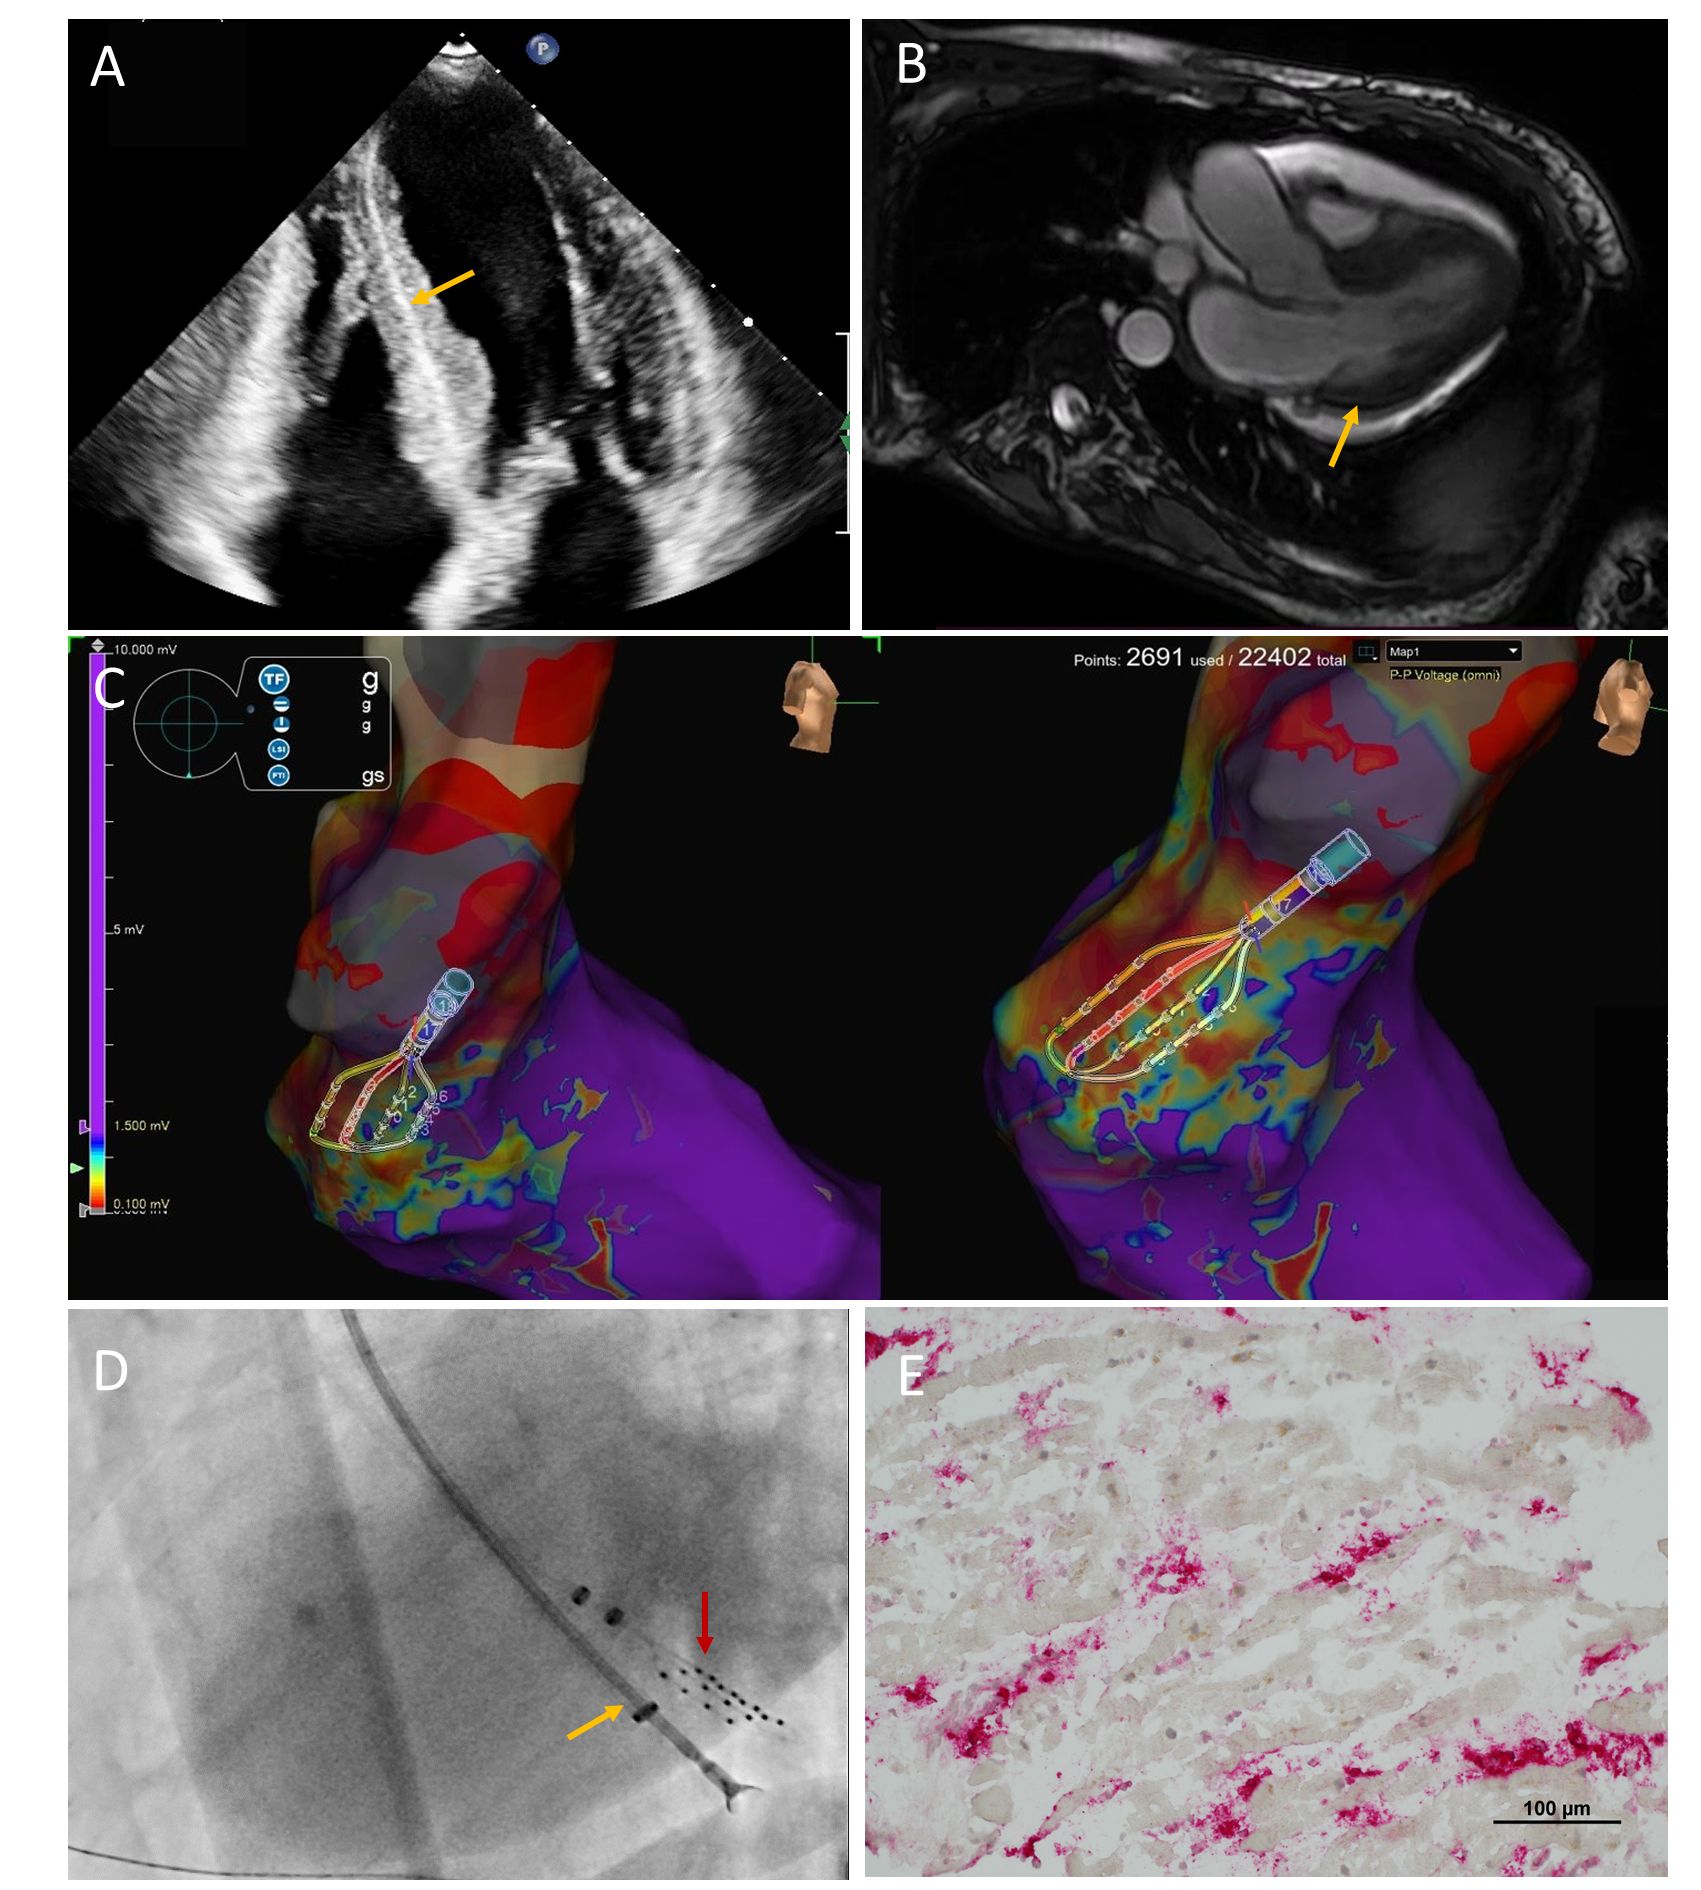

A 53-year-old female was admitted to the cardiology department on account of signs and symptoms of congestive heart failure (HF) with severe peripheral edema and dyspnea on exertion (New York Heart Association class III) for the past 3 months. Her recent past medical history revealed diagnosis of chronic lymphocytic leukemia (CLL) on chlorambucil treatment. Initial laboratory tests revealed slightly elevated N-terminal-pro-B-type natriuretic peptide of 157 pg/mL, hyperleukocytosis (22.2 x 1000/µL; 72% lymphocytes), normal troponin, C-reactive protein concentration, and polyclonal immunofixation pattern. Transthoracic echocardiography showed preserved left ventricular systolic function with the presence of akinesia in the basal segment of the inferior and posterior wall, pericardial fluid layer of 14 mm, asymmetrical left ventricular hypertrophy (septal wall thickness 18 mm), normal atrial size, and hyperechogenic intra-wall left ventricular band (Figure, A [arrow]).

Cardiac magnetic resonance imaging showed intramural late gadolinium enhancement and edema within the inferior-septal and inferior wall of the left ventricle (LV), suggestive of infiltration in the course of leukemia (Figure, B [arrow]). Given the suspicion of CLL infiltration, we performed a guided LV biopsy. Following administration of 5000 IU of unfractionated heparin via intravenous bolus, a transaortic 3D electro-anatomical voltage mapping was performed via the left common femoral artery (8 French [Fr]). The procedure was performed with an Advisor HD Grid mapping electrode with EnSite X system (Abbott), which denoted a low-voltage area within posterior-basal and inferior-basal segments of LV (Figure, C). The mapping electrode was left in this area as a landmark and subsequently a 6-Fr endomyocardial bioptome via 8-Fr multipurpose guiding catheter was introduced via the left common femoral artery (8 Fr); 7 myocardial specimens were acquired from the low-voltage zone (Figure, D; red arrow: mapping electrode; yellow arrow: bioptome). The arterial access sites were successfully sealed using an 8-Fr Angio-Seal device (Terumo).

Immunohistological staining of the endomyocardial biopsy samples showed active myocarditis with evidence of mixed fibrosis in Masson trichrome stain, lack of typical leukemic infiltrates, and negative Congo stain (Figure, E; red: CD68 (+) macrophages adhered to injured cardiomyocytes). The procedure confirmed that there was no sign of CLL involvement in the myocardium, and we proceeded with chlorambucil treatment. In addition, the patient received a complex HF pharmacotherapy including high dose loop diuretic, spironolactone, sacubitril-valsartan, dapagliflozin, and beta-blocker, leading to significant and persistent clinical improvement.